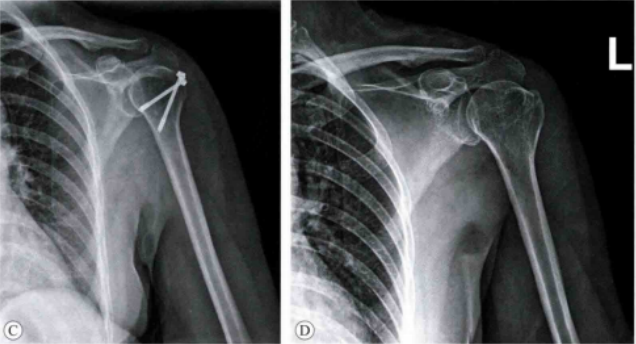

肱骨大结节骨折 ORIF,术前 X 线片显示肱骨大结节骨折情况;术中暴露肱

肱骨大结节骨折 ORIF,术前 X 线片显示肱骨大结节骨折情况;术中暴露肱